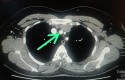

: tronco braquial cefálica

: arteria carótida izquierda

: clavícula

: vena cava